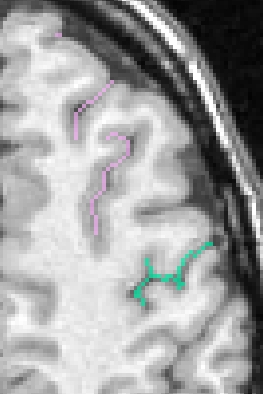

Each fold includes several buckets of voxels corresponding to the topologically simple surface making up its core (GREEN), its bottom lines (including branche's bottoms) (RED) and a few additional voxels corresponding to small or spurious branches (CYAN). Here is the example of a central sulcus: